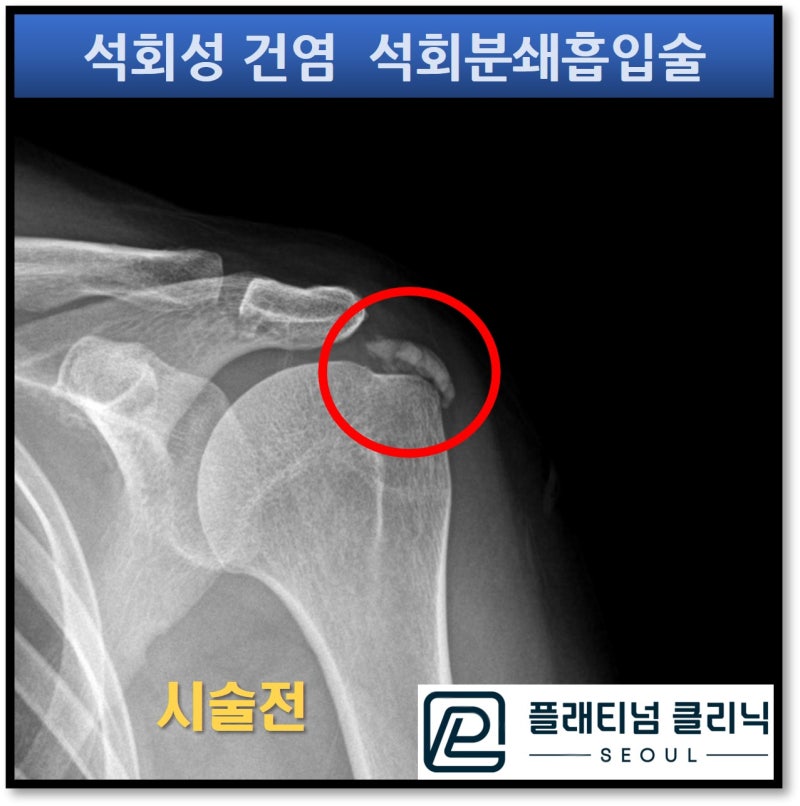

X-ray 사진을 보면 빨간 원안에 하얗게 보이는 커다란 석회가 있습니다. 초음파를 통해 석회의 크기와 양상을 체크해 보았습니다.

석회의 세로길이가 2.0cm, 가로길이가 1.85cm 정도 되는 커다란 석회가 관찰됩니다. 그리고 초음파상 석회의 모양이 거의 보이는 것으로 보아 찐득한 양상의 석회로 판단됩니다. 이렇게 너무 찐득한 석회일 경우 주사기의 얇은 구멍으로 석회가 빠져 나오기가 힘든 경우가 많습니다. 그래서 환자분이 이전병원에서 주사기로 석회를 흡입해내는 것이 실패했을 가능성이 있습니다. 이러한 경우 저만의 기술로 석회를 조금 묽게 만들어 주는 용액을 주사하고 특수제작된 가이드와 드릴을 이용하여 석회를 분쇄하고 흡입내 내면 석회를 잘 제거할 수 있습니다. 석회분쇄흡입술하는 초음파 영상을 보여드리겠습니다.